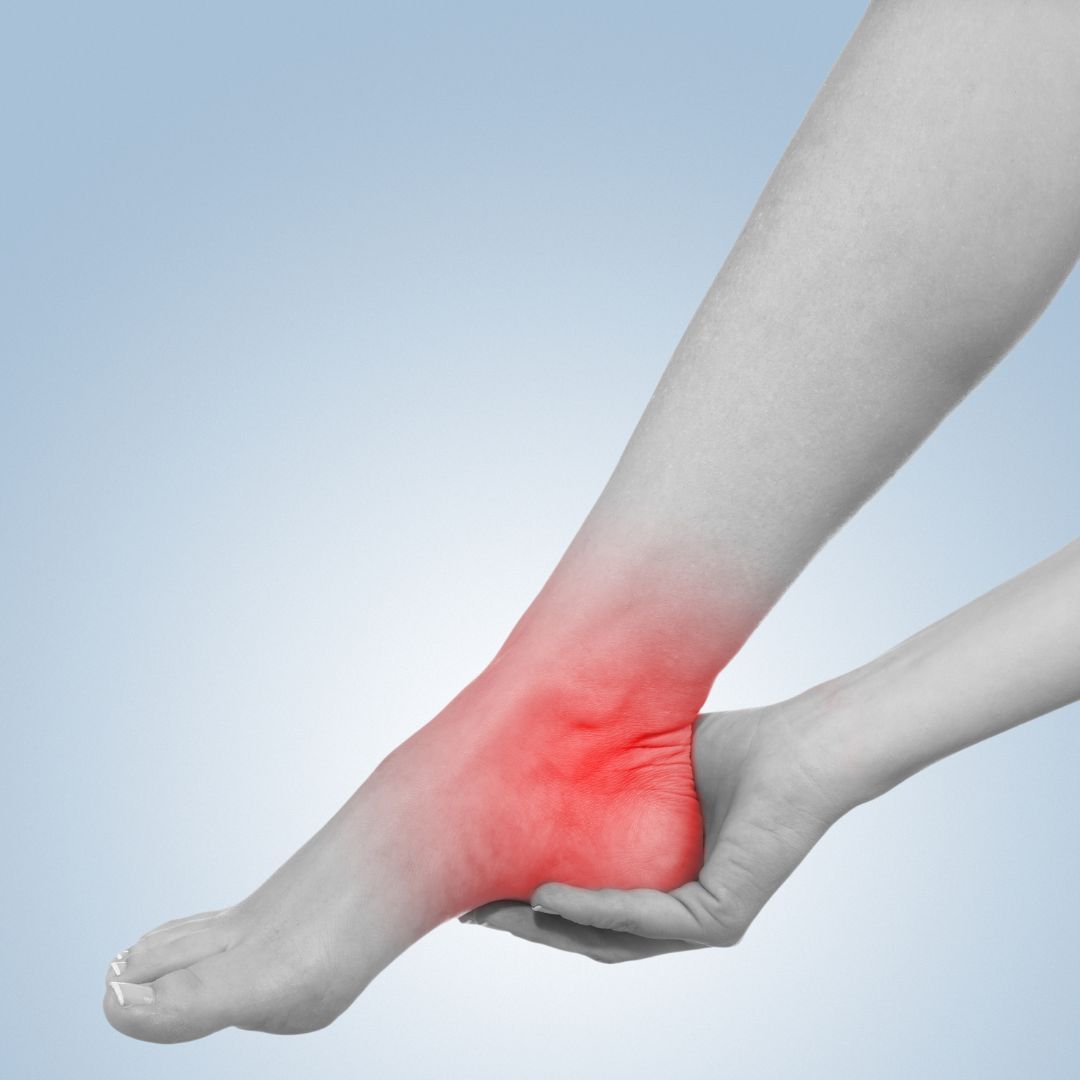

MASAJE TRANSVERSO PROFUNDO APLICADO A LIGAMENTOS:

Los ligamentos son los mayores estabilizadores articulares, están compuestos principalmente de tejido conectivo denso regular, formado por fibras de colágeno tipo I, organizadas en haces paralelos para proporcionar resistencia a las fuerzas de tracción. También contienen fibroblastos (células encargadas de la síntesis del colágeno) y una pequeña cantidad de elastina, lo que les da cierta elasticidad pero, con un predominio de la rigidez.

Cuando un ligamento sufre un

esguince, se produce una distensión o rotura parcial de sus fibras de colágeno lo que conlleva:

- Pérdida de tensión original: El nuevo colágeno se deposita de forma más desordenada y con menor densidad de fibras.

- Mayor laxitud: El ligamento cicatrizado puede quedar más laxo, disminuyendo su capacidad de estabilización.

- Menor capacidad de respuesta propioceptiva: Se dañan terminaciones nerviosas responsables del control neuromuscular.

- Riesgo de recidiva: Un ligamento que ha sufrido un esguince tiene mayor probabilidad de lesionarse nuevamente.

Por ésto, tras un esguince es fundamental un buen protocolo de rehabilitación, en ARTRODINÀMIC además de la terapia manual incluímos el fortalecimiento muscular y ejercicios propioceptivos para compensar la posible pérdida de estabilidad del ligamento afectado. Y en relación al tratamiento CYRIAX protocolizamos dependiendo de si la lesión es AGUDA O CRÓNICA:

- En una lesion aguda mediante la técnica evitaremos que se generen adherencias haciendo tratamiento en posición neutra del ligamento de unos 2 minutos de duración al principio y con una progresión de aumento de tiempo hasta llegar a los 10-15 minutos.

- Ante una lesión crónica aplicaremos una fricción más fuerte durante10 -15 minutos de tratamiento en posición ligamentosa de estiramiento y acompañaremos de movilizaciones articulares al finalizar.